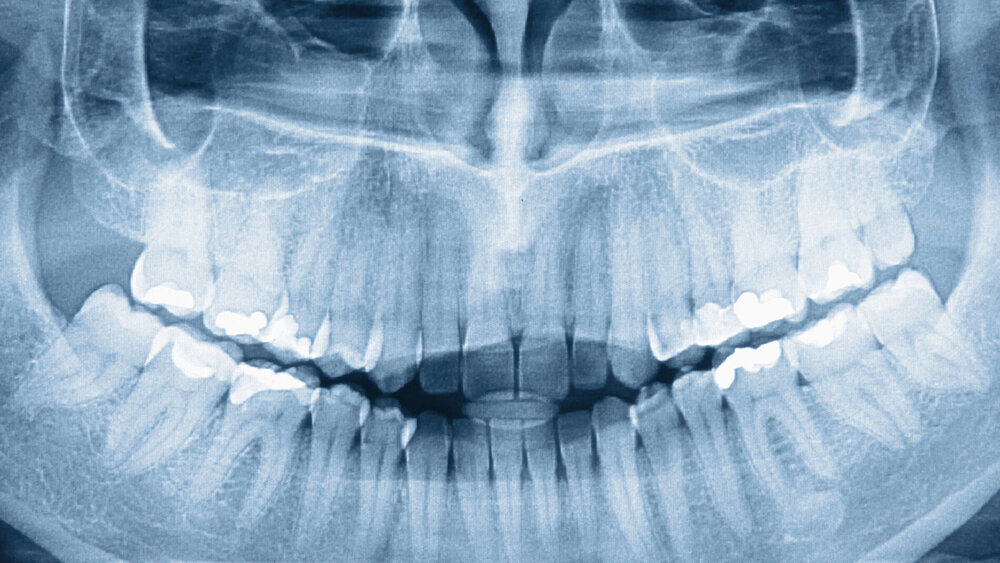

135 Millionen Röntgenuntersuchungen jährlich

In Deutschland werden laut BfS etwa 135 Millionen Röntgenuntersuchungen jährlich durchgeführt, im Schnitt wird jeder Deutsche also 1,7 Mal pro Jahr geröntgt. Die daraus resultierende Strahlenbelastung liegt bei rund 1,6 Millisievert. Zum Vergleich: Die durchschnittliche natürliche Strahlenbelastung, der eine Person in Deutschland im Schnitt im Jahr ausgesetzt ist, beträgt 2,1 Millisievert.